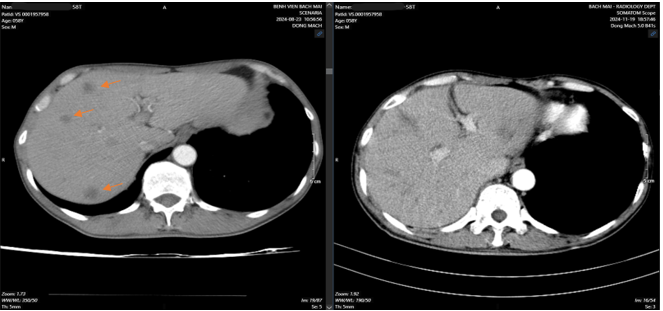

CT bụng: Nhu mô gan hai bên có nhiều nốt giảm tỷ trọng trước tiêm, ngấm thuốc kém kích thước 15x19mm. Dày cành trong tuyến thượng thận trái.

Sau 4 đợt truyền hóa chất, trên hình ảnh CT bụng, xuất hiện các nốt ngấm thuốc kém nhu mô gan hai bên, tổn thương giảm kích thước so với phim chụp 8/2024.